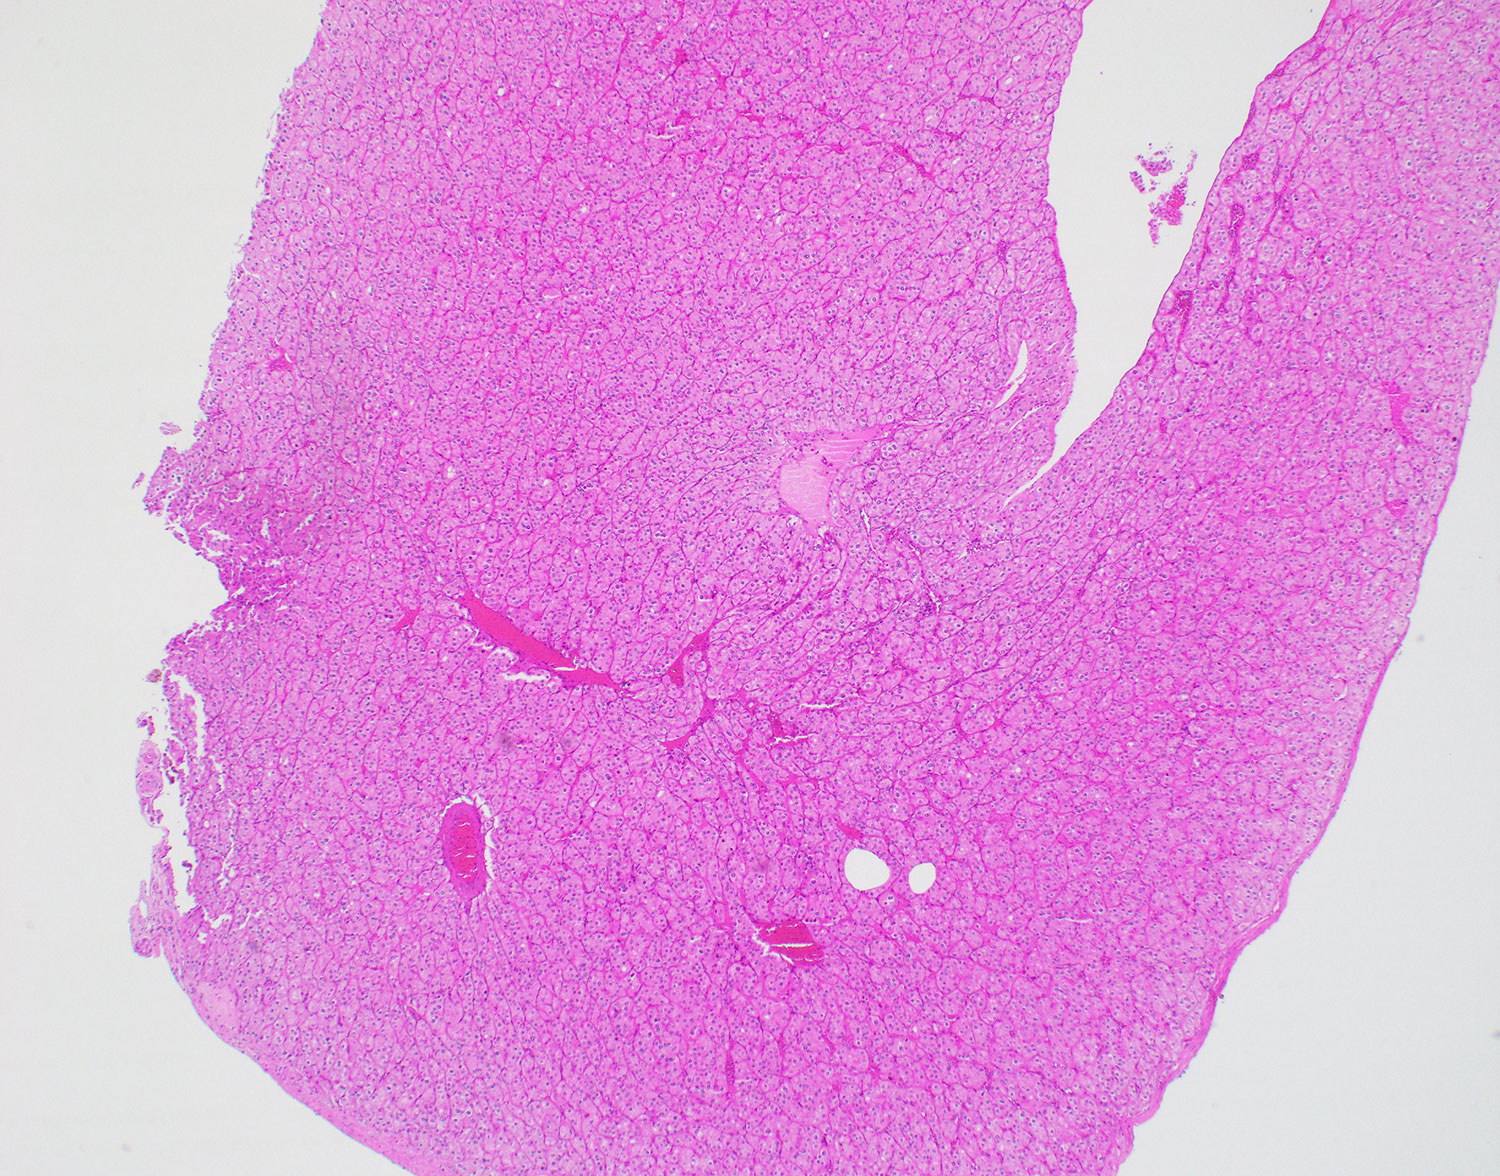

Gross examination of the nephrectomy specimens revealed that the parenchyma of the bilateral kidneys was entirely replaced by innumerable thin-walled cysts. One of the cysts within the right kidney had a calcified and slightly thickened wall.